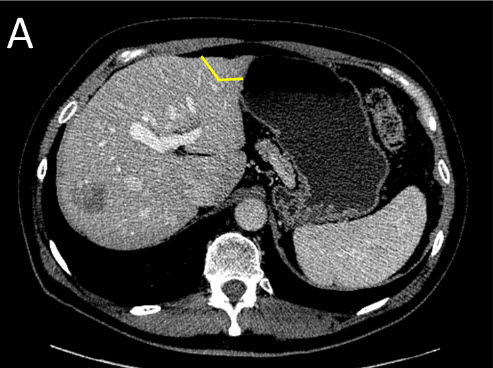

| (A) Staged Liver Resection: First Surgery (Stage I) - the tumors on the future remnant liver are treated first by resection or ablation |